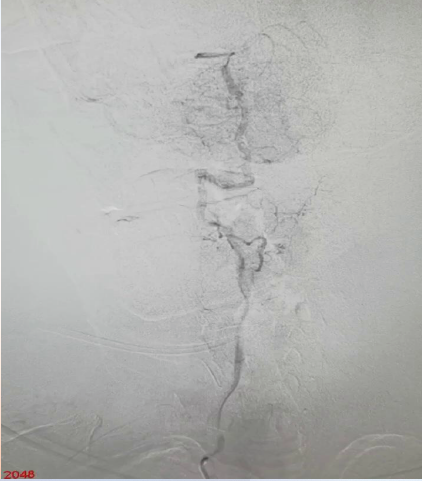

手术过程

在Synchro微导丝与Rebar-18支架导管的辅助下顺利超选上去,借助Transend导丝使用球囊穿梭技术将Sprinter(3*15)球囊装入血管真腔中。

过程影像

病历夹什么径技·第152期|串联营病历夹:川陕大营_https://www.jmylbn.com_新闻资讯_第83张

病历夹什么径技·第152期|串联营病历夹:川陕大营_https://www.jmylbn.com_新闻资讯_第84张

<<滑动查看下一张图片>>

由于guiding通过失败所以先处理近端,将Spider FX(5)保护伞置入进行了远端保护,近端放置了WALLSTENT支架,然后收伞,顺势将guider通过,结果其无法到达远端。

病历夹什么径技·第152期|串联营病历夹:川陕大营_https://www.jmylbn.com_新闻资讯_第85张

病历夹什么径技·第152期|串联营病历夹:川陕大营_https://www.jmylbn.com_新闻资讯_第86张

狭窄段用四个球囊后扩张,将cat6推过狭窄段,发现可能存在远端栓塞,因此将guider退了一下。

病历夹什么径技·第152期|串联营病历夹:川陕大营_https://www.jmylbn.com_新闻资讯_第87张

对侧造影显示,右侧大脑前动脉供血区血流较好。

病历夹什么径技·第152期|串联营病历夹:川陕大营_https://www.jmylbn.com_新闻资讯_第88张

接下来处理远端,Synchro微导丝与Rebar微导管的辅助下,选择置入Solitaire(4-20)支架,支架打开后使用抽拉结合的方式使血管再通。

病历夹什么径技·第152期|串联营病历夹:川陕大营_https://www.jmylbn.com_新闻资讯_第89张

取栓后造影如下:

手术评估

病历夹什么径技·第152期|串联营病历夹:川陕大营_https://www.jmylbn.com_新闻资讯_第90张

病历夹什么径技·第152期|串联营病历夹:川陕大营_https://www.jmylbn.com_新闻资讯_第91张

病历夹什么径技·第152期|串联营病历夹:川陕大营_https://www.jmylbn.com_新闻资讯_第92张